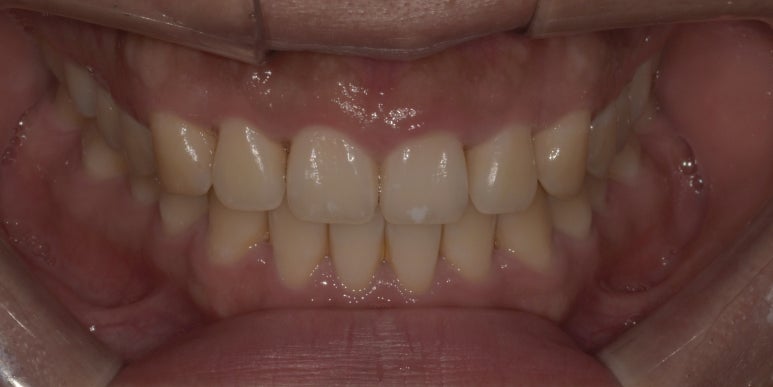

잇몸성형 전후 사진

(전) 2023-05-04 (후) 2023-05-17

위 환자분은 상악 측절치 #12, 22만 다른 치아보다 잇몸이 많이 내려와 있어 다른 치아와의 밸런스를 맞춰주었습니다.